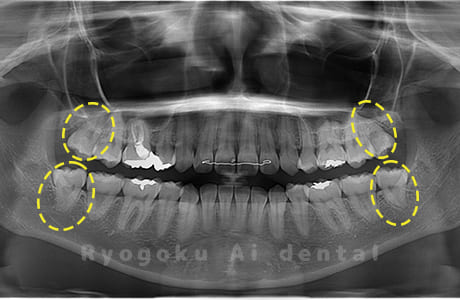

Case04

-

- 原因

- 上顎の親知らず、下顎の水平埋伏の親知らず

- 治療内容

- 上顎の親知らず、下顎の水平埋伏の親知らずを抜歯したケースです。

<リスク・副作用>

手術後は痛み、腫れ、痺れなどの副作用が生じる場合があります。